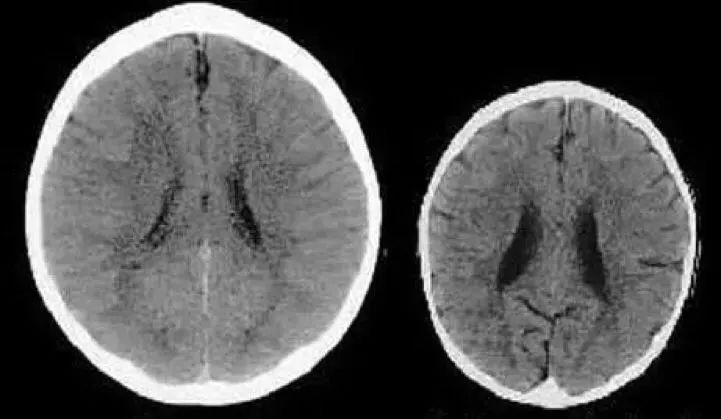

左图(被温柔对待),右图(经常被打骂)

曾经有科学家扫描过两个三岁孩子的大脑图形。(如上图)

其中一个孩子的妈妈性格温柔善良,平时善于和孩子进行有效的沟通。而另一个孩子的妈妈显得非常冷漠,常常忽视孩子的各种需求,甚至虐待自己的孩子。

两个孩子的大脑图形也是千差万别,如上图,左图是第一位孩子的(被温柔以待),右图是第二位孩子的(常被打骂)。

神经学家对图做出来解释,右边图的黑暗区域意味着大脑容量的减少。缺失的区域使孩子会在成长的过程中缺乏思考和智慧,没有同理心等能力。孩子成年后自信心偏弱,事业的竞争欲望较差,缺乏毅力等。

而左边的孩子明显和右边相反。他更懂得理解和包容,心地善良,长大后更自信,更容易成功。